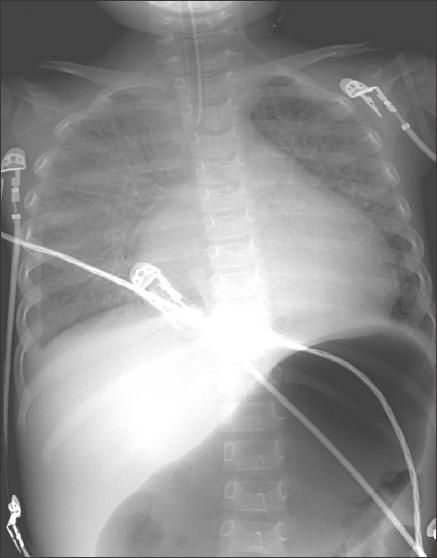

Figure - X-ray film shows endotracheal tube at tip of carina, cardiomegaly, patchy densities, and increased air in stomach.

Chest film as shown.

Chest films show cardiomegaly, interstitial pulmonary edema, or an engorged pulmonary venous pattern. In this patient's case, the chest film showed an endotracheal tube at the tip of the carina, cardiomegaly, patchy densities, and increased air in the stomach.